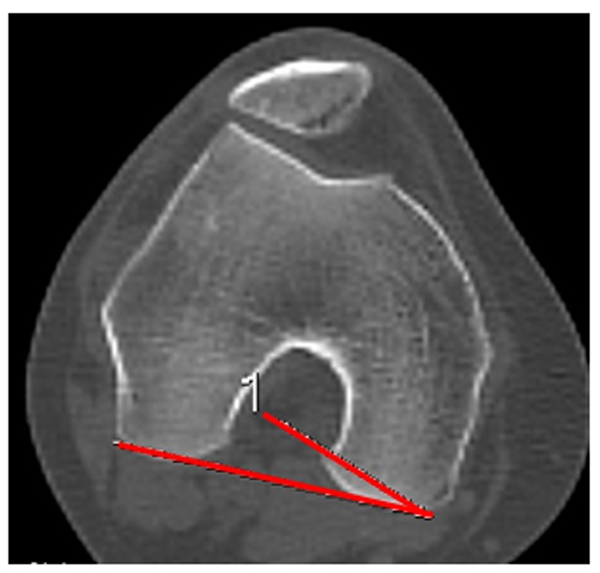

Rotación de la rodilla (femorotibial)

Esta medición se realiza en extensión de rodilla. La rotación de la rodilla se determina al superponer dos imágenes: el corte de línea bicondílea, donde se visualiza el platillo tibial en su mayor diámetro transversal. Se traza la línea bicondílea y otra que delimita el borde posterior de la tibia proximal. El ángulo formado por la intersección de las líneas corresponde con la rotación de la rodilla femorotibial. Valor normal de 3.2°.9, 15 Es importante diferenciar esta “rotación” del fémur en relación con la tibia, de la “torsión de la rodilla en su conjunto” en relación con el miembro y la dirección de avance del cuerpo a la cual denominamos “torsión de rodilla” (fig. 12).

Figura 12: Rotación femorotibial. Se mide luego de la superposición de dos cortes de cóndilos femorales donde se visualiza el arco romano, y corte de tibia proximal donde se ve máximo el ancho. Ángulo con la intersección de línea bicondílea y línea paralela al borde cortical posterior tibial. Normal: de 3 a 5°.